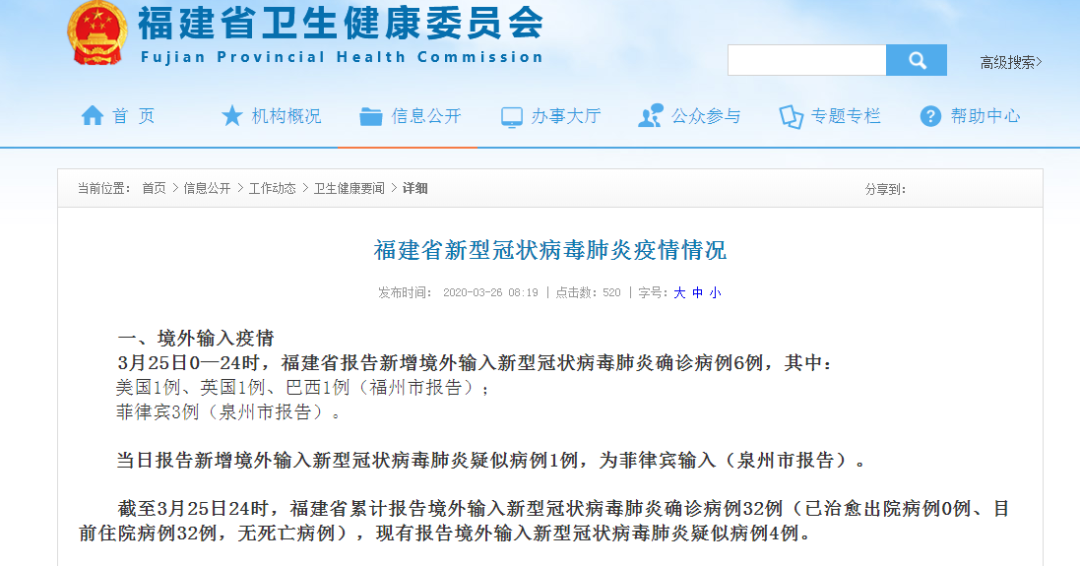

境外冠状病毒最新消息更新,全球疫情动态通报

摘要:最新境外冠状病毒通报显示,全球疫情形势依然严峻,多个国家和地区出现病毒传播。目前,各国政府和卫生机构正在积极采取措施应对,加强防控力度,以保障公众健康安全。具体疫情情况需关注官方发布的最新消息和数据。自XXXX...